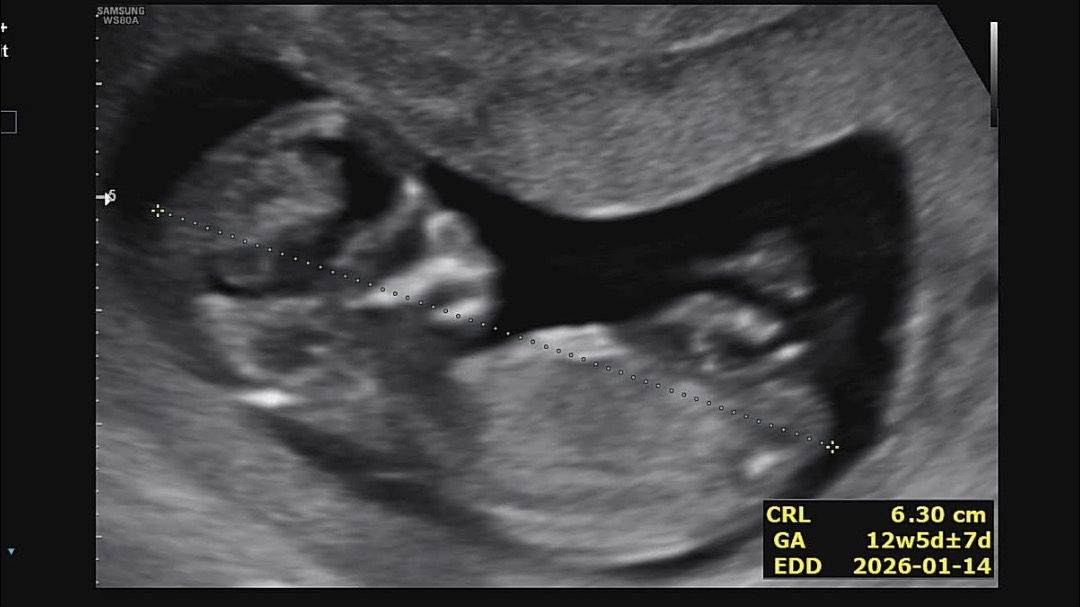

12주차 5일 각도법 부탁드려요~~~

살짝 위로 솟은거 같기두 하구 집이 좁아서 그런가 싶고 허허 재미로 봐주세요~